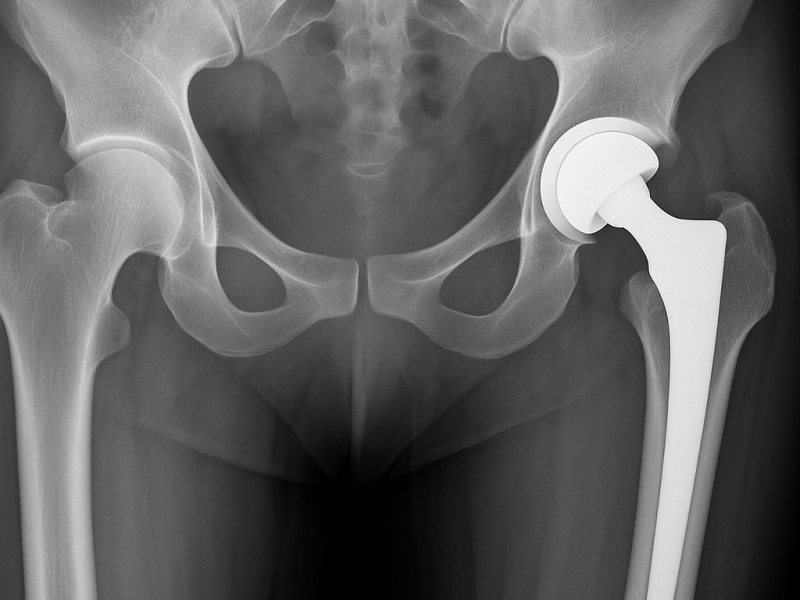

Il dolore all’anca può limitare ogni aspetto della vita quotidiana: camminare, salire le scale, dormire serenamente, praticare attività fisica.La protesi totale di anca rappresenta oggi una soluzione sicura, efficace e definitiva per ritrovare libertà di movimento e qualità di vita.Grazie a tecniche chirurgiche evolute e a un percorso altamente personalizzato, accompagniamo il paziente verso un recupero stabile, rapido e duraturo.

La scelta dell’accesso chirurgico è un momento fondamentale dell’intervento e viene effettuata in modo mirato, in base alle caratteristiche anatomiche e agli obiettivi funzionali del paziente.

Ogni intervento è preceduto da un’attenta valutazione clinica e da una pianificazione pre-operatoria dettagliata. Nulla è lasciato al caso.

L’obiettivo è offrire al paziente la soluzione più adatta alle sue esigenze, riducendo il dolore e favorendo un ritorno rapido e sicuro alle attività quotidiane.